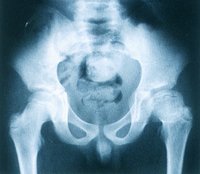

疾病預後

高雪氏病:A.股骨密度減低,皮質變薄,遠端輕度擴張,呈“燒瓶樣”畸形。B.胸腰段椎體變扁楔變,脊椎後突畸形,骨質疏鬆。Ⅱ型多發於發病1年內死於繼發呼吸道感染,少數可存活2年以上。Ⅲ型在神經系統狀出現後,逐漸消耗,並有運動障礙,多死於反覆發作的繼發感染。Ⅰ型進展很慢,脾切除後可存活至正常人的年齡,智力完全正常。

起病隱匿,病程緩慢,常以肝脾大和貧血就診。隨病情進展,可出現皮膚、眼和骨關節症狀,但無神經系統症狀。按病情進展可分三期:①初期:一般狀況好,僅有脾腫大和輕度正色素貧血,生長發育接近正常。②中期:肝臟亦逐漸增大,但不如脾大明顯。淺表淋巴結多不腫大。隨著貧血的加重,面色逐漸蒼白。由於脾功能亢進,白細胞和血小板亦多減少,網路紅細胞輕度增高。在暴露部位的皮膚呈現特殊的棕黃色。部分病人骨關節症狀出現較早,可有骨和關節隱痛。③晚期:各型症狀逐漸加重,貧血顯著,白細胞與血小板明顯減少,粒細胞甚至可低至10000/L以下,常合併感染和有皮膚黏膜出血傾向。淋巴結亦可輕度腫大。若肝臟浸潤嚴重,可出現肝功能損害,甚至肝硬化,食道靜脈曲張和凝血因子的減低,尤其Ⅸ因子缺乏比較多見。骨和骨髓浸潤可致骨痛,關節腫痛,有時需與風濕性關節炎鑑別。Ⅹ線檢查可見髓腔增寬、普遍性骨質疏鬆,並可見局限性骨質破壞;典型所見是股骨遠端膨大,有如燒瓶樣,常合併股骨頸和脊椎壓縮性骨折。化骨核癒合較晚。兩眼球結膜出現對稱性棕黃色楔形斑塊,其底在角膜邊緣,尖端指向眼眥,先見於鼻側,後見於顳側,此征多隻見於成年人,兒童較少見。此類患兒身高及體重多在正常低限。